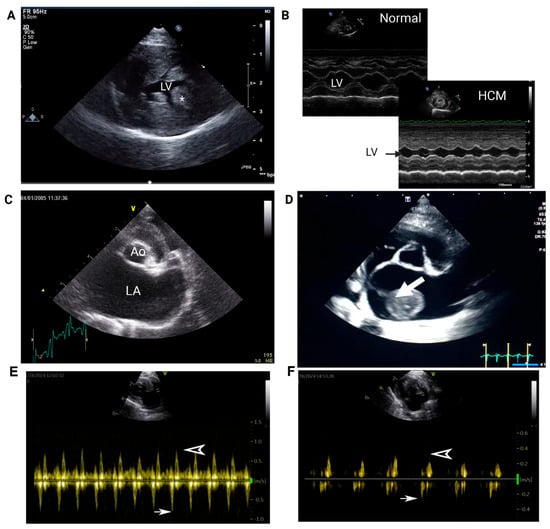

| Echocardiogram | LV systolic dysfunction (LV fractional shortening and emptying fraction) |

| LA systolic dysfunction (Low LAA velocity, Low LA fractional shortening) | |

| Spontaneous echocardiographic contrast and/or intracardiac thrombus | |

| LA enlargement (LA:Ao > 1.6) | |